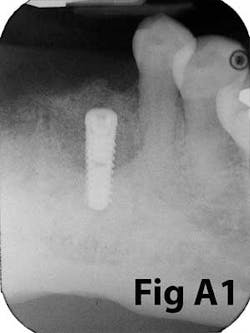

Fig. 6: Implants placed in lateral window sinus graft with no augmentation of attached tissue.